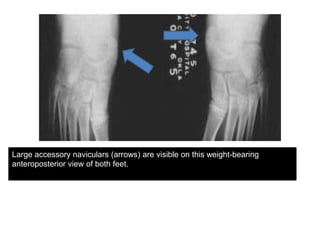

Large accessory naviculars (arrows) are visible on this weight-bearing

anteroposterior view of both feet.

• 13. Large accessory naviculars (arrows) are visible on this weight-bearing anteroposterior view of both feet.